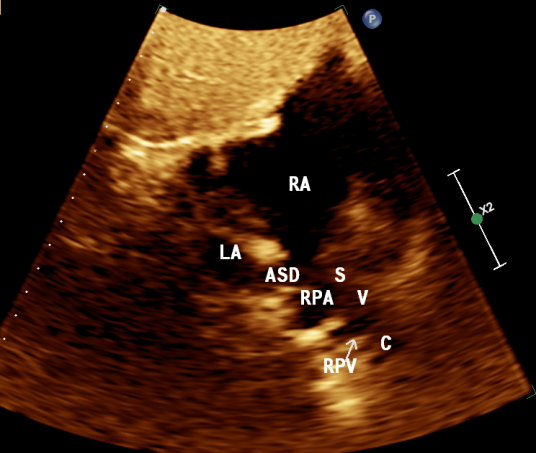

图 5 右上肺静脉进入上腔静脉-右房入口处